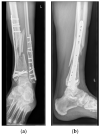

Innovative techniques can help overcome the limitations of the human body. Operating on very small structures requires adequate vision of the surgical field and precise movements of sophisticated instruments. Both the human eye and hand are limited when performing microsurgery. Conventional microsurgery uses operation microscopes to enhance the visualization of very small structures. Evolving technology of high-definition 3D cameras provides the opportunity to replace conventional operation microscopes, thereby improving ergonomics for surgeons. This leaves the human hand as a limiting factor in microsurgery. A dedicated robot for microsurgery has been developed to overcome this limitation and enhance the precision and stability of the surgeons' hands. We present the first-in-human case in reconstructive microsurgery where both technologies are integrated using a dedicated microsurgical robot in combination with a 4K 3D exoscope.